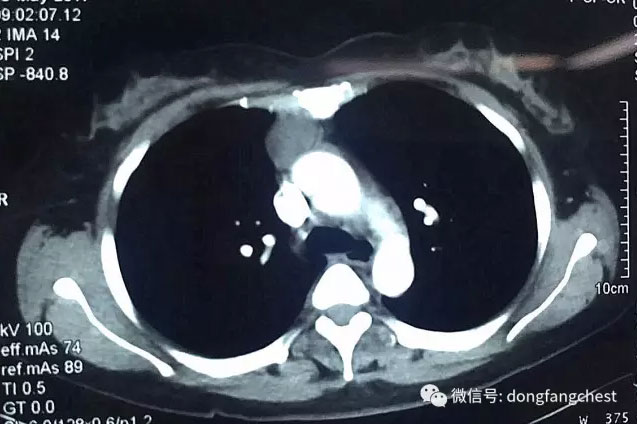

淮南市本地患者张女士今年57岁,2年前体检时发现前纵隔肿物,自从发现胸腔内的长了肿物后,张女士倍感压力,经常觉得各种不适。今年4月,张女士入院再次复查CT发现,胸腔内肿物较之前明显增大,这更让张女士和她的家人十分担心,甚至寝食难安。

经多家医院就诊咨询后,张女士选择入住东方总院胸外科进行治疗。经过术前详细的检查和针对张女士“糖尿病、高血压病”的调整准备后,以朱胜、王鸿主任为首的胸心外科团队为张女士安排了“单孔胸腔镜纵隔肿物切除”手术。为最大程度减少患者的损伤以及切口的美观,主刀医师王鸿主任仅在2cm长的小切口下就成功完整切除了约6cm大小的纵隔肿瘤,手术过程仅耗时半个多小时,手术几乎没有出血。